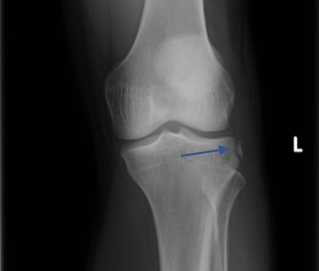

Lesson 3 / When you see a Segond fracture, you know for sure that there is an ACL rupture.

What a little beauty this one is. You wiggle the knee, call it an ACL, get the x-ray, spot the Segond fracture, and then it’s a hi-five FIGJAM moment. Or else it’s your first week in the clinic, all the knees still feel the same, and then the x-ray saves you.

The fracture is seen quite easily in the x-ray below and is caused by rotational forces in which the lateral retinaculum produces a small avulsion fracture. The fracture in itself is irrelevant, but it just so happens that any twisting injury severe enough to create this fracture has already ruptured the ACL.